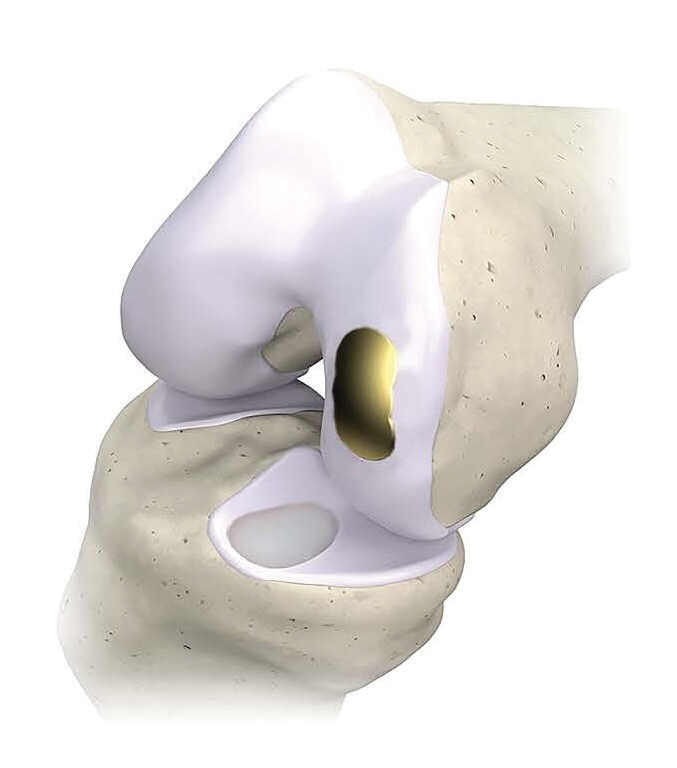

Femoral and tibial components of the OvertureTi Knee Resurfacing System®. The implants’ baseplates are made of 3D-printed, porous titanium to promote osseointegration and solid fixation. Articulating surfaces for the femoral and tibial components are titanium nitride and an overmolded vitamin E-treated, highly crosslinked polyethylene, respectively. (Image courtesy Overture Orthopaedics, PRNewswire)

The knee resurfacing system is composed of femoral and tibial implants that are intended to be used in partial replacement of articular surfaces of the knee, according to a release accompanying the launch. The implants were designed with sizing options that allow surgeons to replace only the diseased or damaged region of the joint—while preserving healthy surrounding cartilage and meniscus—in a procedure known as Focalplasty®.

The baseplates of the implants are 3D printed of porous titanium to promote osseointegration and solid fixation. Articulating surfaces for the femoral and tibial components incorporate titanium nitride and an overmolded, vitamin E-treated, highly crosslinked polyethylene, respectively. The implants are a fraction of the cost of biological options, the company said in the release.